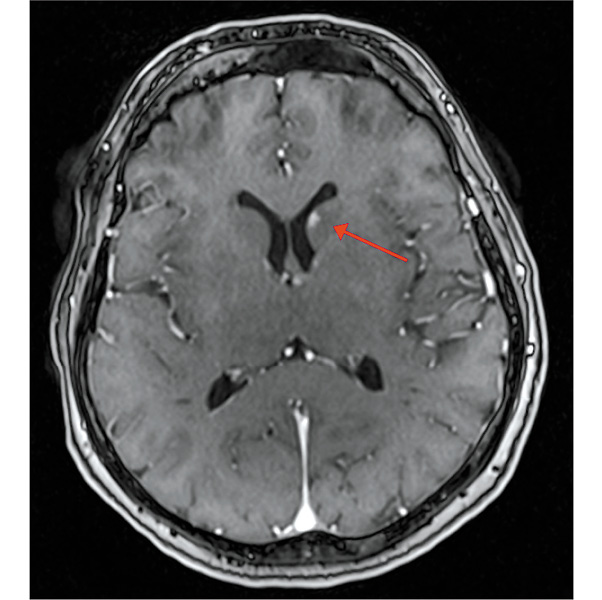

Пациентка продолжала исследуемую терапию, когда в марте 2018 г. на МРТ головного мозга с в/в контрастированием по поводу периодически беспокоящих головных болей выявлен единичный мтс в области головки хвостатого ядра левого полушария большого мозга до 5 мм без перифокального отека (рис. 7). По всей видимости, этот очаг обнаружен случайно, поскольку такой небольшой мтс не должен вызывать симптомы, что обусловливает необходимость регулярного обследования головного мозга у пациентов с распространенной меланомой при помощи МРТ с в/в контрастированием (в процессе терапии и несмотря на достижение глубокого радиологического ответа).

Рис. 7. МРТ головного мозга с в/в контрастированием от 03.2018 г.